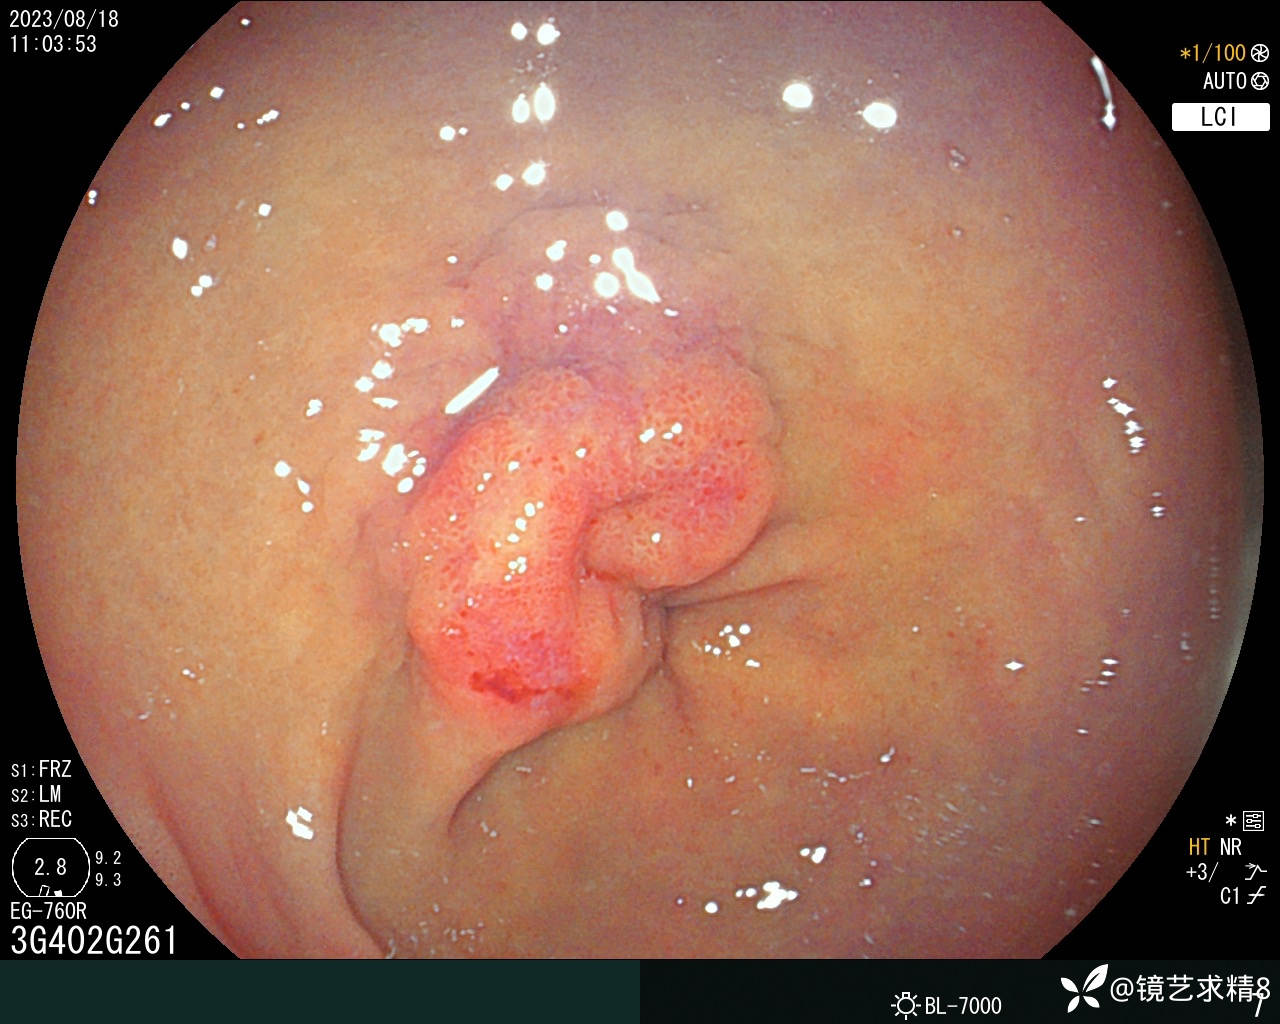

胃窦:黏膜红白相间,前壁与小弯侧交界近幽门见一0-Ia+IIc型病变,约20*30mm大小,BLI染色局部呈淡茶色,边界可见,表面结构欠规则,取病检2块+HP检查,质软。

内镜下诊断:1. 胃窦0-Ia+Ic型病变,不除外早期ca?请结合病检+HP检查